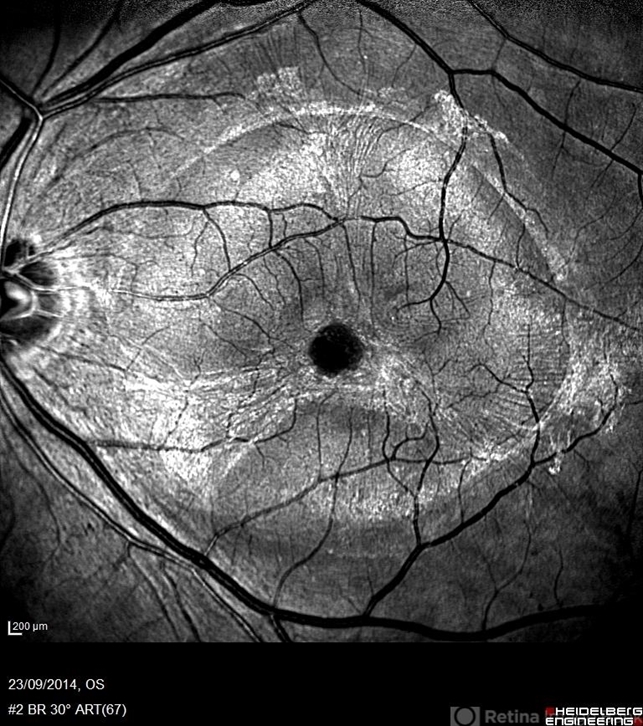

- pigment epithelial detachment (PED), red-free

- Avris Romario Diparaja Siahaan, Klinik Mata Nusantara

Scanning laser ophthalmoscope

Heidelberg Spectralis - Description

- A red free fundus photograph of a 74-year-old man with pigment epithelial detachment in his left eye.